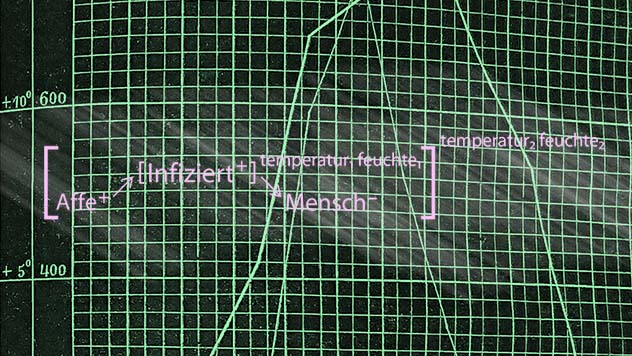

Epidemiological Diagrams (2015-)

'Diagrams of Epidemiological Knowledge' (Formerly: 'Epidemics and Topological Experience') is a PhD research project in the field of Media Studies at the University of Hamburg. It was supported by the Research Training Group 'Loose Connections - Collectivity in Digital and Urban Space'. The project traces different forms of diagrammatic media and mediators in the recent history and practice of epidemiologists, especially maps, causal diagrams, and threshold visualizations in automated surveillance. The project combines archival research and expert interviews with epistemological problematizations in media theory and philosophy.